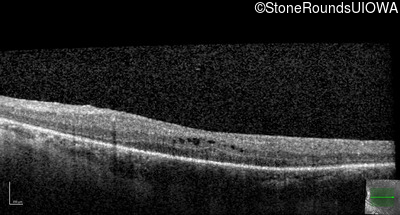

Optical Coherence Tomography - Left - 20/50

Exemplar / OCT Stack